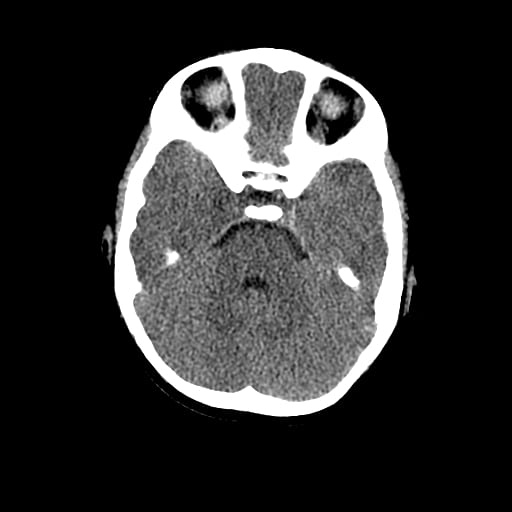

Age: 1

Sex: Male

Indication: Fall